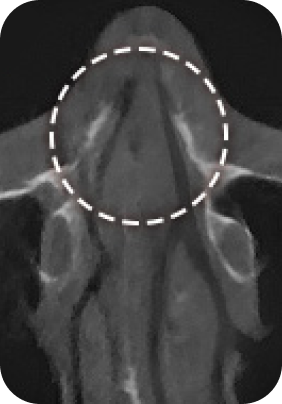

맘모톰, 비후성/알레르기 비염, 비중격 만곡증, 비밸브 협착증 등

질환에 따라 3DCT, 내시경 검사, 고해상도 초음파를 통해 정밀진단 후

정확한 증상에 따라 보험 실비 청구가 가능합니다.

대학병원급 검사 장비

유방외과 전문의 / 이비인후과 전문의

디에이성형외과에서는 대학병원급 검사 장비 시스템

각 분과의 전문의와 성형외과 전문의가 협진하여